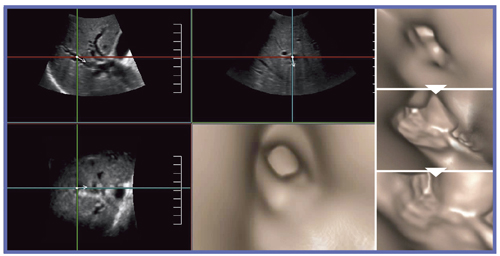

Fly Thruは,管腔内の視点から管腔壁を見るように表示できるアプリケーションで,膵管,胆管,尿管,血管,乳管,消化管など,幅広い領域で用いられる。中枢から末梢へ,あるいは末梢から中枢へと,任意の方向から,管腔内をあたかも飛ぶように観察することができる(図1)。

図1 Fly Thru画面

67歳,女性,肝内胆管・総胆管拡張(十二指腸乳頭がん)

4Dプローブ「PVT-675MV」を用いて取得したボリュームデータを元に映像化し,視点は任意の管腔内を中心線に沿って移動する(図2)。自動走査と手動走査を選択でき,断層像を同時に表示することで内部構造も観察できる。従来の超音波3Dは,無限遠に視点を置いた平行投影法であり,奥行き感をつかむことが難しかった。それに対し,Fly Thruは遠近法に準ずる画像表示法であるため,内視鏡的な画像を表示することが可能となっている(図3)。図4のような数mmのポリープも,隆起性病変として明瞭に表現することができる。